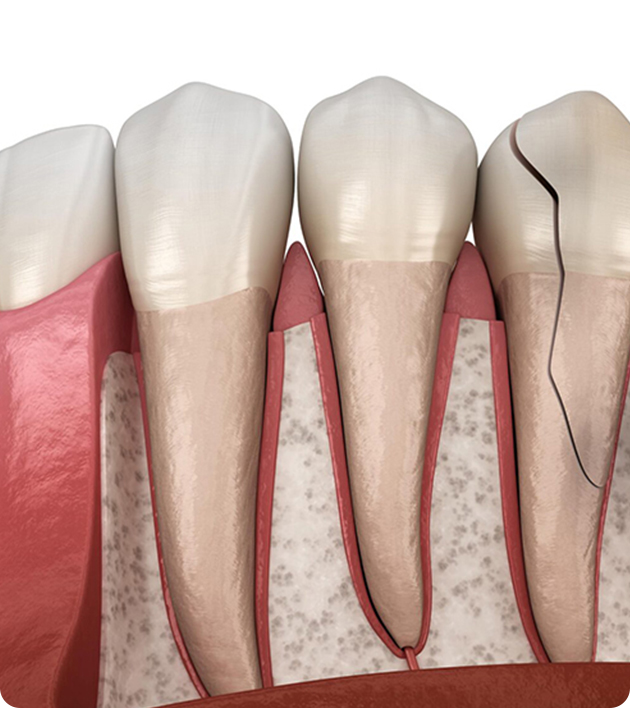

Wisdom teeth extraction is a common dental surgery performed to remove one or more third molars—known as wisdom teeth—that usually appear between the ages of 17 and 25. These teeth can cause issues if there isn’t enough space for them to grow properly.